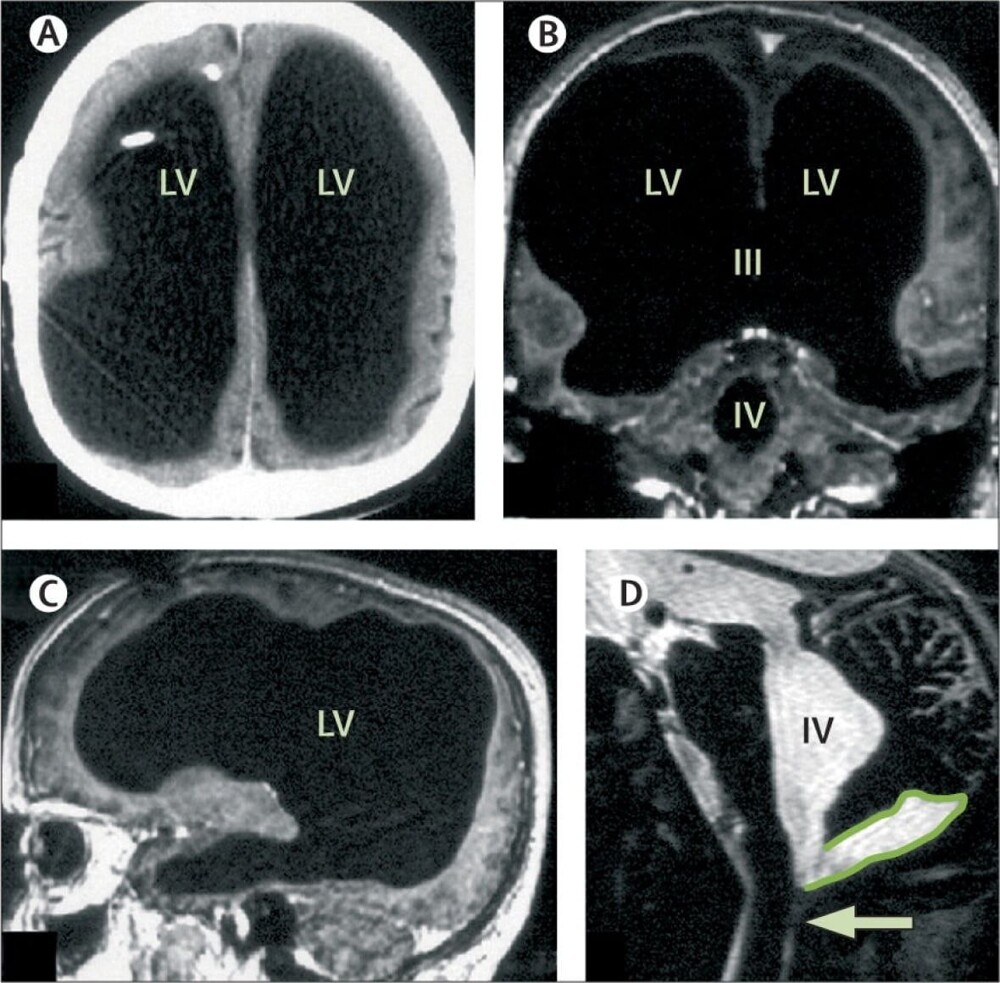

In a 44-year-old man, the skull was full of fluid, and from the brain only the thinnest layer of brain tissue remained. He did a brain scan for the first time and did not even suspect that something was wrong with him.

Scientists zealously undertook to investigate the patient and came to the conclusion that that his brain was slowly being destroyed in a process called dropsy of the brain, or, in scientific terms, hydrocephalus. Diagnosis the man was put in as a teenager and had a bypass, to restore the movement of cerebrospinal fluid.

But at the age of 14, the shunt was removed and the brain began to gradually die off, as the fluid continued to accumulate in it.